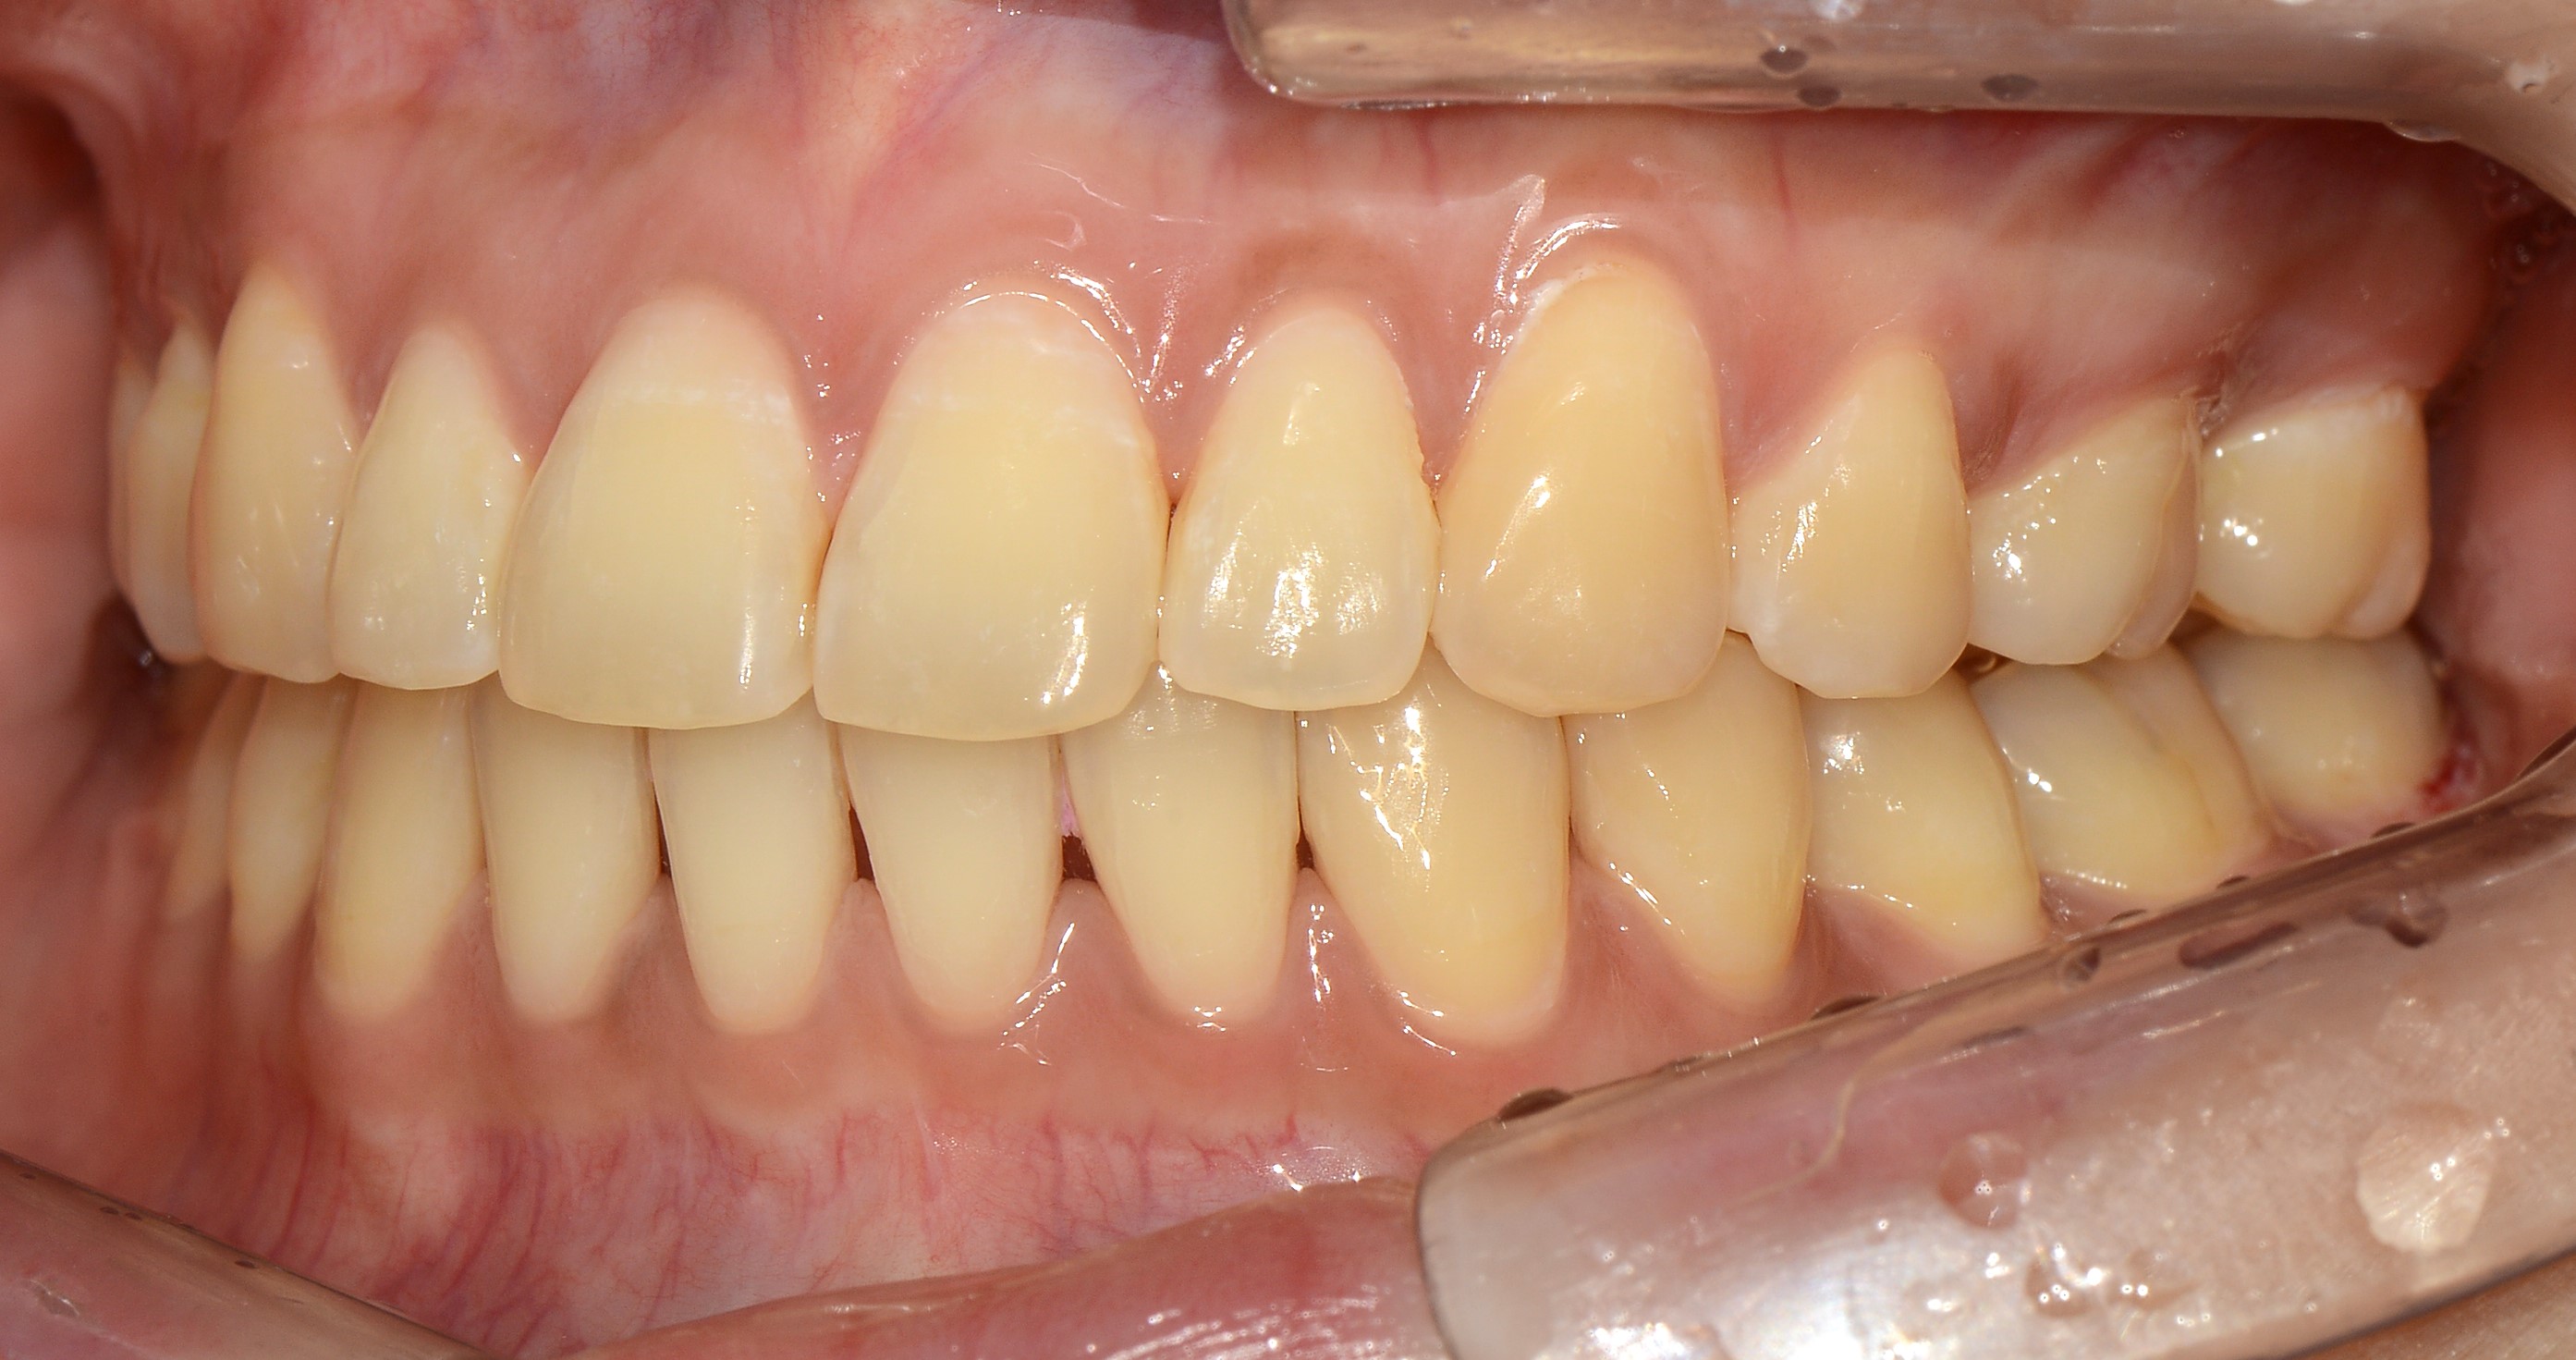

치료 전 사진입니다.